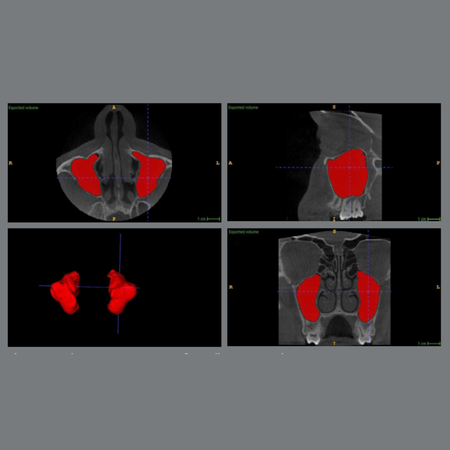

Volumetric changes in the maxillary sinus following orthodontic disimpaction of unilaterally impacted maxillary canines: a prospective CBCT-based split-mouth study

Introduction: The relationship between orthodontic disimpaction of unilaterally impacted maxillary canines (MCs) and volumetric changes in the maxillary sinus (MS) remains underexplored. Objective: This study aimed to evaluate MS volume alterations following orthodontic traction of impacted MCs, using cone-beam computed tomography (CBCT). Additionally, it examined differences based on the impaction site (buccal vs. palatal) and sex. Material and Methods: A prospective split-mouth study was...

Alterações volumétricas no seio maxilar após desimpacção ortodôntica de caninos superiores impactados unilateralmente: um estudo prospectivo de boca dividida baseado em tomografia computadorizada de feixe cônico

Introdução: A relação entre a desimpacção ortodôntica de caninos superiores (CSs) impactados unilateralmente e as alterações volumétricas no seio maxilar (SM) permanece pouco explorada. Objetivo: Este estudo teve como objetivo avaliar as alterações volumétricas do SM após a tração ortodôntica de CSs impactados, utilizando tomografia computadorizada de feixe cônico (TCFC). Adicionalmente, examinou as diferenças com base no local da impacção (vestibular vs. palatina) e no...